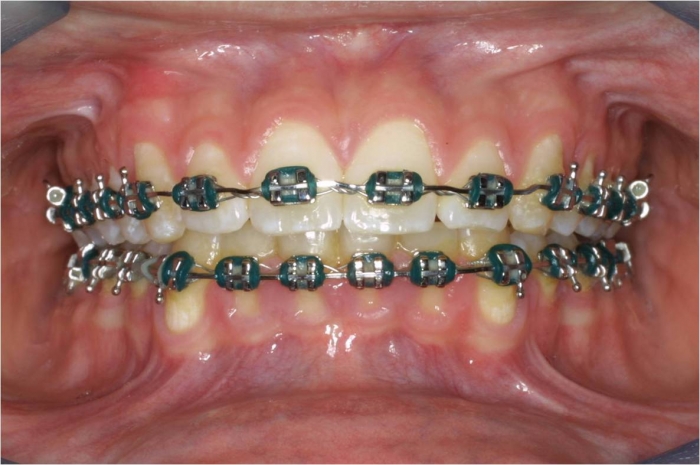

Mordida inicial

Mordida após cirurgia